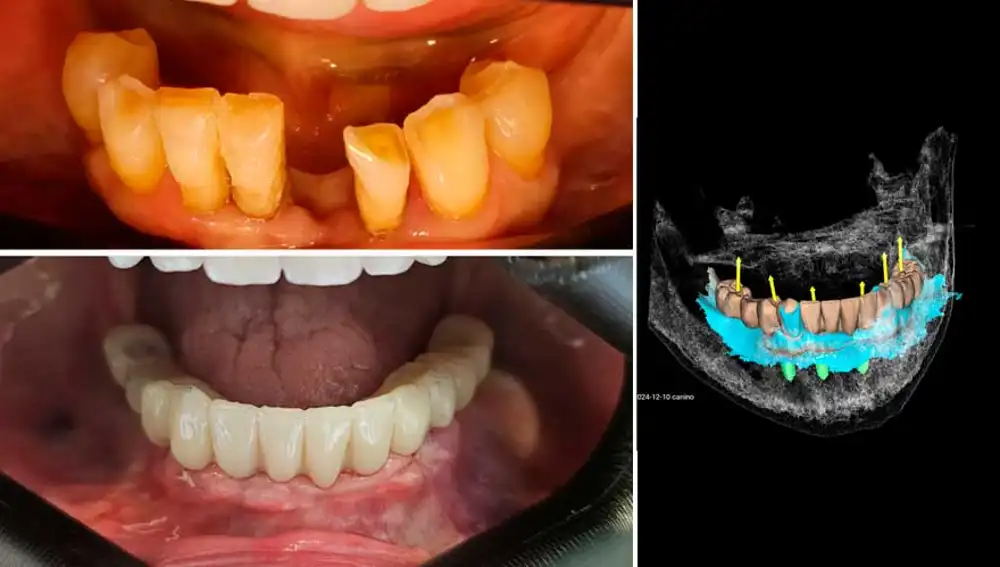

La cirugía guiada de implantes es una técnica avanzada en implantología dental que ofrece numerosos beneficios para una rehabilitación completa de la boca. Esta técnica utiliza tecnología de imagen 3D y software especializado para planificar y ejecutar la colocación de implantes con gran precisión y de manera mínimamente invasiva para el paciente: conseguimos mayor seguridad, altísima precisión, y la mayor comodidad para el paciente, que con esta técnica las molestias de la intervención quedan reducidas al mínimo.

El proceso para el paciente es muy sencillo, ya que nuestro equipo de profesionales le hará un escáner 3D (en nuestro caso CBCT, más avanzado que un simple TAC) de su boca y elaboraremos un modelo 3D digital. Sin entrar en demasiados tecnicismos, las imágenes de la boca del paciente se fusionan en un software de planificación dental, de esta manera el Dr. García del Olmo planificará virtualmente la posición óptima de cada implante.

Tras ello, se enviará a laboratorio protésico en el que diseñaremos y fabricaremos una guía quirúrgica personalizada mediante impresión 3D. Esta guía es la que colocaremos en la boca del paciente, y permitirá a nuestro implantólogo dirigir la colocación precisa de cada implante.